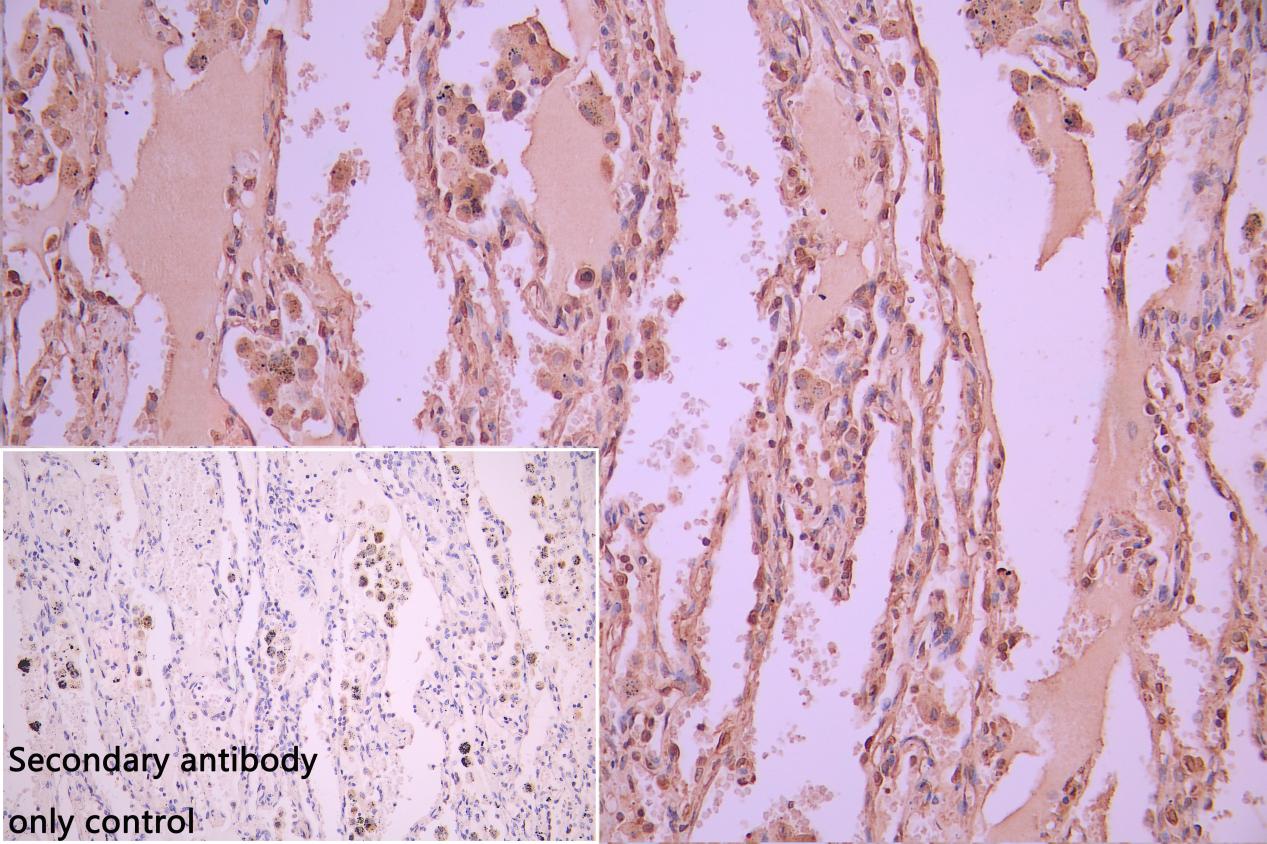

IHC image of CSB-PA896505DSR2HU diluted at 1:50 and staining in paraffin-embedded human Lung cancer performed on a Leica BondTM system. After dewaxing and hydration, antigen retrieval was mediated by high pressure in a citrate buffer (pH 6.0). Section was blocked with 10% normal goat serum 30min at RT. Then primary antibody (1% BSA) was incubated at 4°C overnight. The primary is detected by a Goat anti-rabbit polymer IgG labeled by HRP and visualized using 0.05% DAB. Secondary antibody only control: uses 1% BSA instead of primary antibody